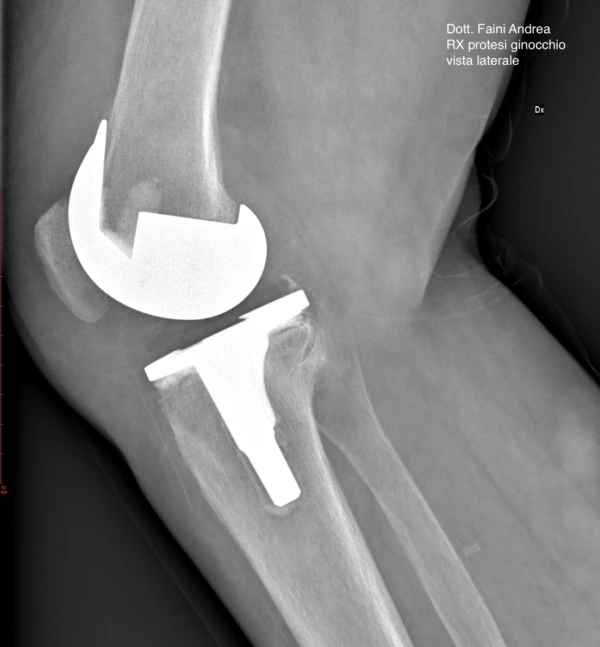

- Artroplastica: sostituzione protesica di un’articolazione.

Chirurgo Ortopedico, laureato in Medicina e Chirurgia e specialista in Ortopedia e Traumatologia. Mi occupo di chirurgia dell’anca e del ginocchio, con ultraspecializzazione nella protesica di primo impianto e di revisione.